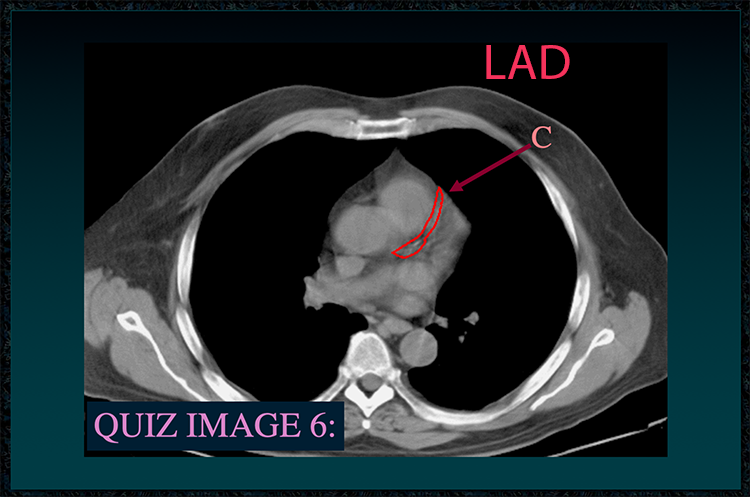

◂Chest Anatomy Review